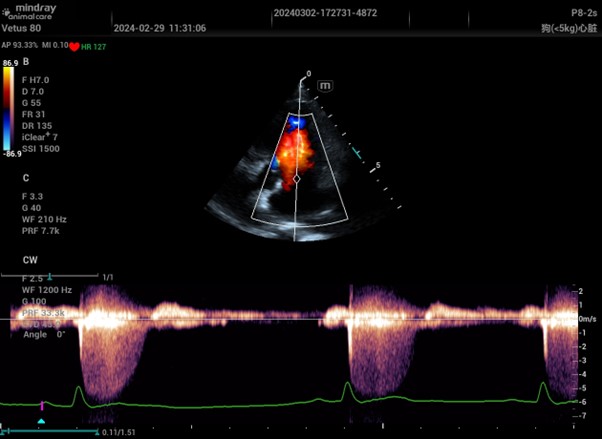

Continuous Waver Doppler image from Mindray Vetus 80

Continuous Wave Doppler lives up to its name by transmitting sound continuously, using two separate crystals in the transducer, one for sending and one for receiving. This continuous transmission allows the system to measure extremely high velocities, essentially without an upper limit, making it ideal for detecting fast blood flow that exceeds the Nyquist limit of Pulsed Wave Doppler.

Unlike Pulsed Wave Doppler, which produces velocity ‘envelopes’ due to its region-specific sampling, Continuous Wave Doppler measures all velocities along the entire sound path. This results in a filled spectral trace that includes both high and low velocities. The trade-off is a loss of spatial specificity, you can’t determine exactly where along the line the flow originates. For this reason, it’s often best to first localise the area of interest using Colour Doppler or Pulsed Wave Doppler before applying Continuous Wave.